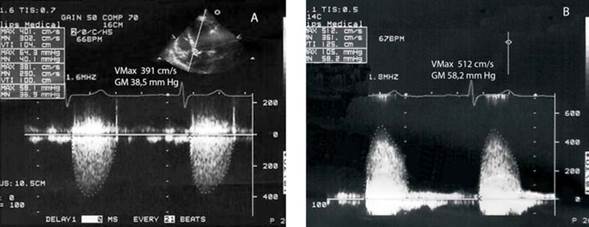

Cuando se catalogó la EA solamente por ÁPEX (Tabla 4), 56 fueron clasificadas como severas y 44 como no severas (33 como moderadas y 11 como leves). La utilización del enfoque PED reclasificó como severas 18/33 (54,6%, IC 95% 36,4-71,9) que eran moderadas por ÁPEX (Figura 1) y 3/11 (27,3% IC 95% 6,0-61,0) leves por ÁPEX (Figura 2) . En total 21/44 (47,7%) de las EA no severas por ÁPEX fueron reclasificadas como severas por PED, es decir uno de cada dos pacientes.

Figura 3 Registros desde ÁPEX y PED en el mismo paciente. A: ÁPEX con valores de VMáx y GM de EA moderada. B: PED con Pedof con VMáx y GM correspondientes a EA muy severa.